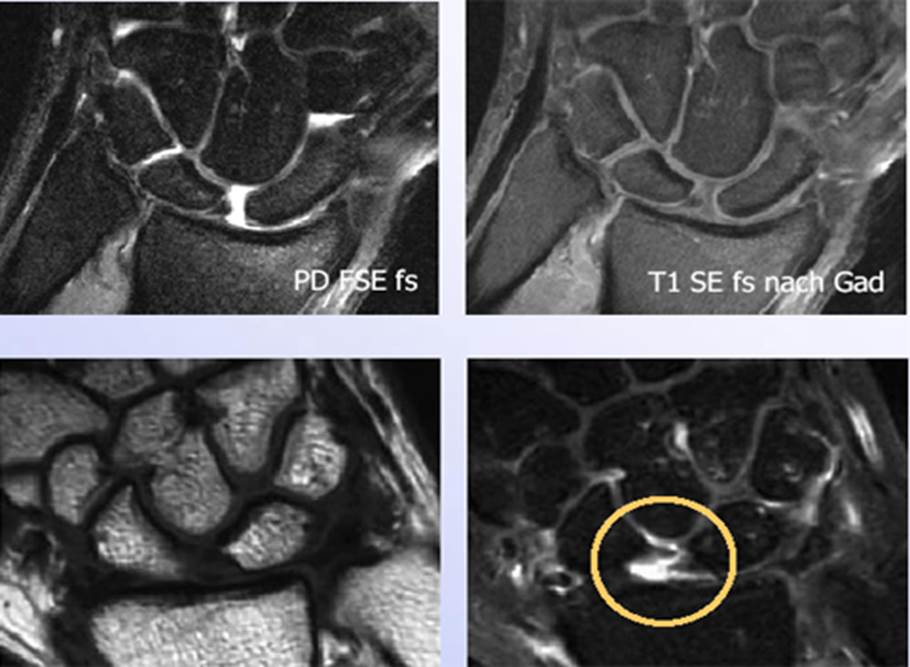

Mondbeinnekrose Handchirurgie

Bandverletzungen An Der Hand